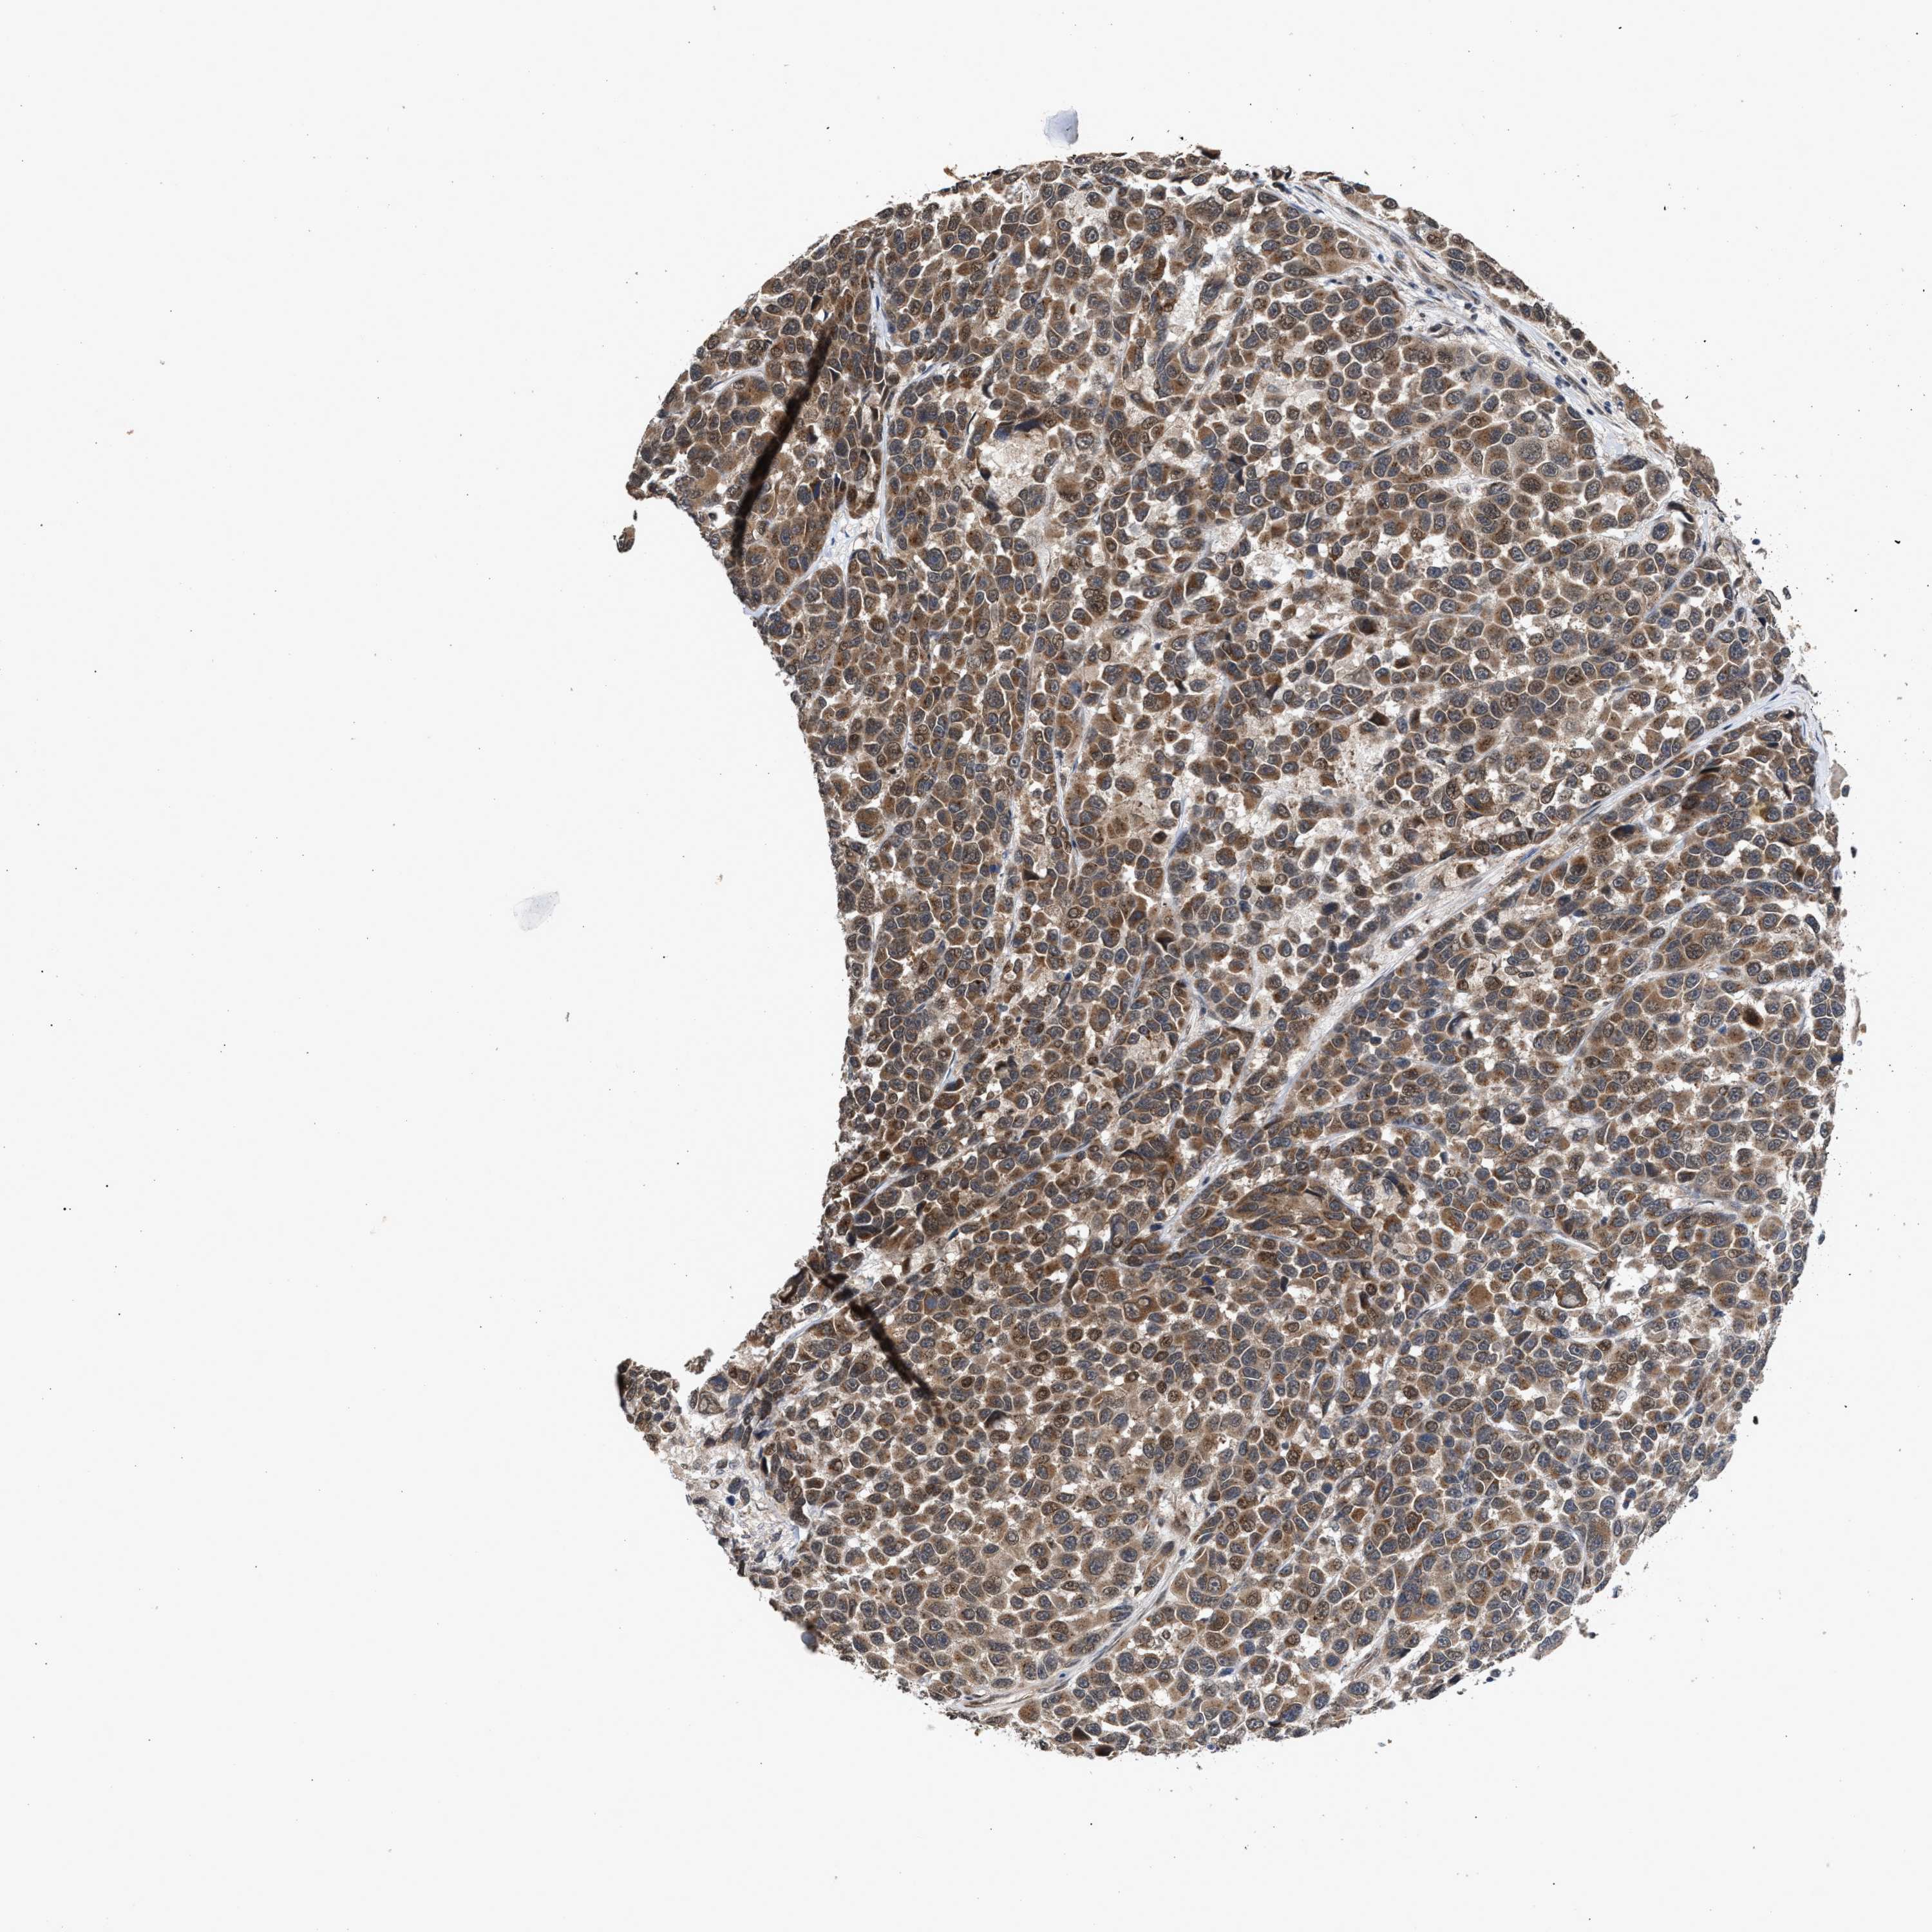

MELANOMA - Protein expressioni

A mouse-over function shows sample information and annotation data. Click on an image to view it in a full screen mode. Samples can be filtered based on level of antibody staining by selecting one or several of the following categories: high, medium, low and not detected. The assay and annotation is described here.

Note that samples used for immunohistochemistry by the Human Protein Atlas do not correspond to samples in the TCGA dataset.

Antibody stainingi

Antibody staining in the annotated cell types in the current human tissue is reported as not detected, low, medium, or high, based on conventional immunohistochemistry profiling in selected tissues. This score is based on the combination of the staining intensity and fraction of stained cells.

Each image is clickable and will lead to virtual microscopy that enables deeper exploration of all samples and also displays staining intensity scores, fraction scores and subcellular localization as well as patient and tissue information for each sample.

Antibody HPA021875

Antibody CAB037253

Staining

High

Medium

Low

Not detected

Intensity

Strong

Moderate

Weak

Negative

Quantity

>75%

75%-25%

<25%

None

Location

Nuclear

Cytoplasmic/membranous

Cytoplasmic/membranous,nuclear

Malignant melanoma, NOS

Malignant melanoma, Metastatic site